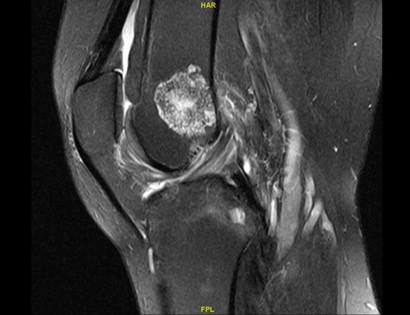

• • The work-up often consists of a physical examination, X-rays, CT scans, MRI, and sometimes bone scans are required.

Radiographic imaging is used to help form a diagnosis. These include X-Ray, MRI, CT and Bone Scans

An example of an enchondroma X-Ray is shown.